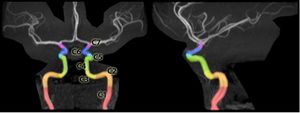

Segments of the internal carotid artery, delineated on an MRA of the head.

C1: القسم القحفي

C2: القسم الصخري

C3: القسم الثُقبي

C4: القسم الكهفي

C5: القسم السريري

C6: القسم الشرايين العينية

C7: قسم الشرايين الموصلة